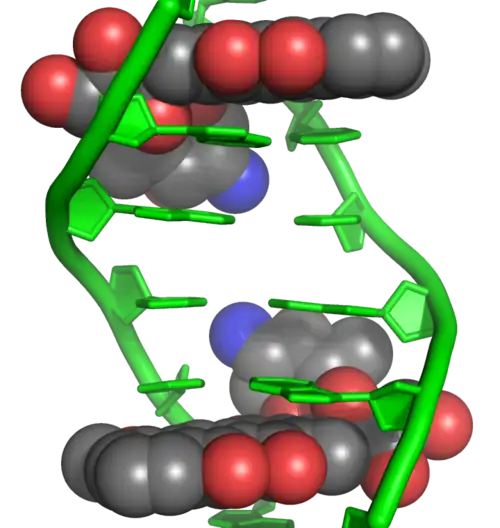

Doxorubicin interacts with DNA by intercalation and inhibition of macromolecular biosynthesis.[11][40][41] This inhibits the progression of topoisomerase II, an enzyme which relaxes supercoils in DNA for transcription.[42] Doxorubicin stabilizes the topoisomerase II complex after it has broken the DNA chain for replication, preventing the DNA double helix from being released and thereby stopping the process of replication.[11] It may also increase quinone type free radical production, hence contributing to its cytotoxicity.[15]

The planar aromatic chromophore portion of the molecule intercalates between two base pairs of the DNA, while the six-membered daunosamine sugar sits in the minor groove and interacts with flanking base pairs immediately adjacent to the intercalation site, as evidenced by several crystal structures.[39][43]

By intercalation, doxorubicin can also induce histone eviction from transcriptionally active chromatin.[44][45] As a result, the DNA damage response, epigenome and transcriptome are deregulated in doxorubicin-exposed cells.[44]